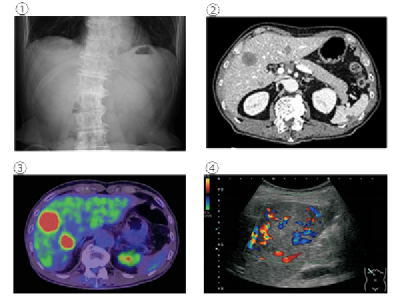

腹部の検査の画像を別に示す。生体の代謝を利用した検査はどれか。

1. ①

2. ②

3. ③

4. ④

① 腹部レントゲン

② 腹部CT

③ PET検査。ブドウ糖代謝を利用している。

④ 腹部超音波検査のドップラー検査。